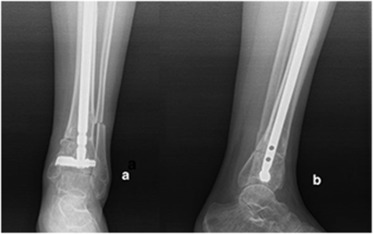

A 39-year-old female had an AO type A2-3 fracture of the tibia with no additional injury. She was treated with Ilizarov frame following distal tibial metaphysis fracture. The Ilizarov frame was removed 7 months postoperatively, and varus deformity was observed. The patient was admitted to our hospital with primary complaint of inability to walk due to the deformity. AP and lateral ankle X-rays were obtained (Fig. 3 a and b).

Fig. 3.

Preoperative AP (a) and lateral (b) , and postoperative AP (c) and lateral (d) X-rays of Patient 2.

A valgus producing open-up osteotomy was performed. One DSBLS was inserted parallel and 3 mm above the ankle joint. The fibula was osteotomized first at the level of the proximal margin of the tibiofibular syndesmosis. Multiple holes were drilled medially 30 mm proximal to the ankle joint; a thin osteotome was used to connect the holes, sparing the lateral cortex, and the medial surface was split by insertion of thin osteotomes into the gap. The appropriate size of the opening wedge was determined on the basis of the preoperative weight-bearing AP radiograph and confirmed using fluoroscopy. Our new IMN (320 × 10 mm) was inserted proximally and improved through the distal fragment. After completing the distal interlocking, the correction was reassessed with the tibiocalcaneal angle under fluoroscopy in neutral position of the ankle. After completing and fixing the osteotomy, iliac graft was collected and packed into the osteotomy gap. The correction was controlled with postoperative AP-lateral X-rays (Fig. 3 c and d).